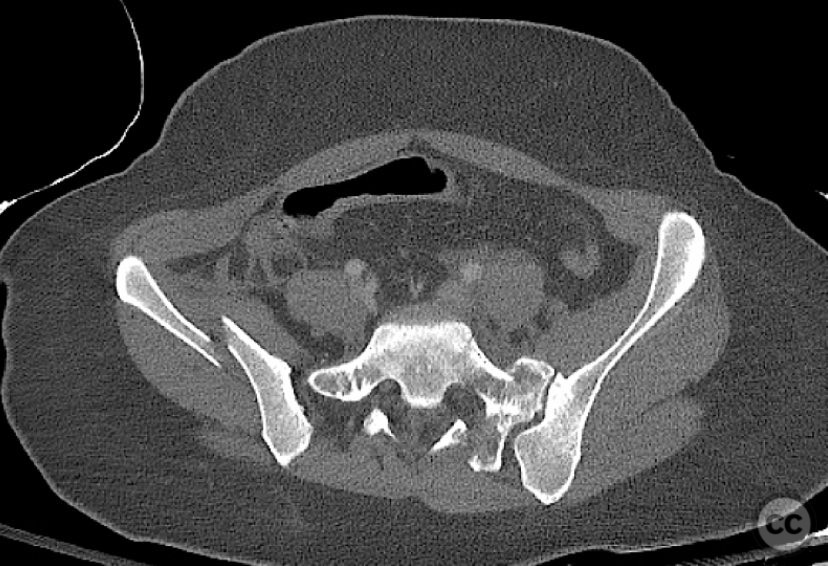

Clinical Details

Clinical and radiological findings:  A 26-year-old female sustained a closed pelvic ring injury following a motor vehicle accident. She was hemodynamically stable, neurologically intact, and had no other associated injuries. Skin integrity was preserved. Initial management included pelvic binder application and 10 pounds of distal femoral skeletal traction. Portable AP pelvic radiograph demonstrated a left-sided sacral fracture with associated ipsilateral iliac wing and pubic ramus fractures, consistent with an AO/OTA 61-B2 (lateral compression type II) injury pattern.

Anatomical surgical approach:  The left sacral fracture was addressed first via percutaneous placement of iliosacral screws under fluoroscopic guidance. An anterior approach to the iliac wing was performed via a longitudinal incision along the crista iliaca, subperiosteal dissection to expose the fractura alae ossis ilii, followed by debridement, reduction, and temporary clamping. Definitive fixation was achieved with two 7mm diameter cannulated fully threaded medullary screws placed across the iliac crest and pelvic brim into the corpus ossis ilii. The left ramus ossis pubis fracture and overall cingulum pelvicum were assessed intraoperatively with fluoroscopy for residual instability.

Intraoperatively, minimal residual deformity of the left hemipelvis was noted after traction and positioning. The sacral fracture was stabilized first with iliosacral screws. The anterior iliac exposure allowed for direct visualization, cleaning, reduction, and clamping of the iliac wing fracture prior to screw fixation. After fixation, intraoperative fluoroscopic stress examination demonstrated stability of the left pubic ramus fracture and overall pelvic ring, obviating the need for further anterior fixation.

Orthopaedic implants used:   Two 7mm diameter cannulated fully threaded medullary screws (iliac crest and pelvic brim), percutaneous iliosacral screw(s).